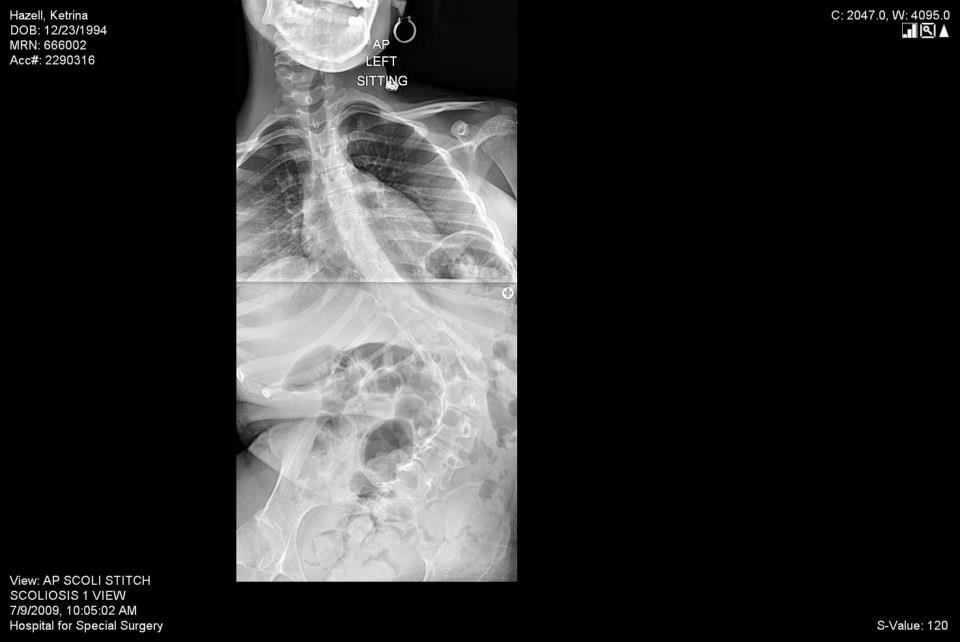

Nearly 5 years later while having Mother’s Day dinner, my brother noticed what seemed to be a hole in my back when checking on me. My mom quickly called HSS and asked if we can see the next available doctor. The next morning, I was at HSS getting x-rays done and waiting to see the doctor, who diagnosed me with scoliosis. I was referred to see Dr. Green, who told us surgery was the next step to correct my scoliosis as my spine was curved at 90-degrees. I began to see many specialists in preparation of my surgery. Honestly, I was emotionally drained in the process of one of the appointments, which was preparing me to use an oxygen machine for the rest of my life. In October 2009, Dr. Green performed the surgery. It took 9 hours, but it was very successful. I refer to it as being given a second chance in life.